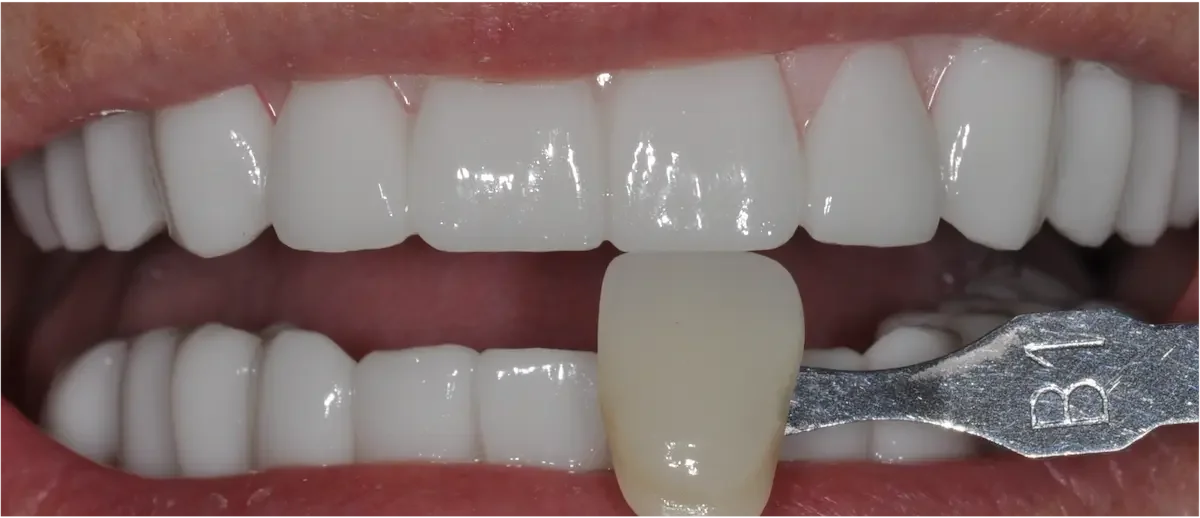

How We Restored a Front Tooth with a Dental Implant — Start to Finish

They’re what people notice first. So when a front tooth is missing or damaged — whether from trauma, decay, or failed restorations — it’s not just about replacing it. It’s about doing it perfectly in the smile.

In this case study, we’ll walk you through one of the more complicated — and rewarding — procedures we do at our practice: a front tooth dental implant. You’ll see how much thought, planning, and precision goes into restoring one small tooth… and why every step in the dental implant process matters.

Unlike molars, where strength matters to a higher degree, replacing a front tooth is has much to do with aesthetics, symmetry, and subtlety, in addition to bite force management.

Here’s why it’s such a technical and artistic challenge:

Any tiny mismatch is obvious. The color, shape, gumline — everything has to match the neighboring teeth.

The bone and gum are thin. That makes it easier for collapse or shadowing to occur.

We’re working in the “esthetic zone.” This area demands precise planning, sculpting, and soft tissue support. Thankfully all our doctors have advanced training in cosmetic dentistry.

Over the next few weeks or months, we monitor soft tissue healing. Sometimes we adjust the temporary to guide gum shaping. Patience here pays off — rushing this stage can lead to esthetic failure. One of the biggest risks in front teeth implants is gum recession!Final Crown

Once everything is stable, we place the final custom crown. Shade, translucency, shape, and surface texture are all matched to your natural teeth so the implant blends in seamlessly.

If all the steps are followed carefully — especially tissue shaping and crown customization — it will be nearly impossible to tell it’s not your original tooth. Check out our video case study to see more.